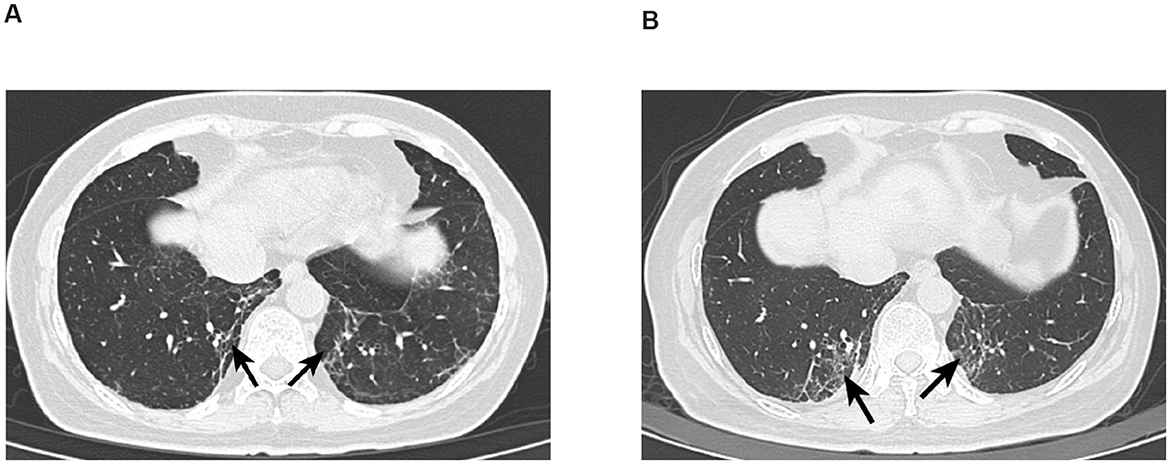

Five months later, she reported dizziness, localized swelling pain on the right parietal scalp, and intermittent nausea. Chest and abdominal CT showed worsening interstitial inflammation in both lower lung lobes (Figure 1A). Follow-up brain MRI indicated that while the cerebellar metastases had slightly regressed, the cerebral lesions had increased in both number and size. Given the progression, she received additional palliative brain radiotherapy (60 Gy/25 fractions) while continuing her existing drug regimen.

Figure 1. (A) CT image of Patient 1 with interstitial lung disease. Absent left breast, consistent with postoperative changes, generally unchanged from previous; follow-up and reexamination recommended. Scattered inflammatory organized foci in both lungs; interstitial inflammation in the lower lobes of both lungs has significantly increased compared to previous. (B) CT image of Patient 1 with interstitial lung disease after 4 months. Postoperative changes in the left breast, generally unchanged from previous, recommend follow-up and reexamination. Scattered inflammatory organized foci in both lungs, increased significantly from previous; improved reexpansion of the lower lobes of both lungs compared to prior, and the previously noted bilateral minimal pleural effusions have now resolved.

Two months later, repeat CT imaging demonstrated increased inflammatory and organizing focal lesions in both lungs (Figure 1B). Concurrently, she developed fever, rash, aggravated myelosuppression, and worsening dizziness. Following multidisciplinary evaluation, dalpiciclib was discontinued, and supportive care (anti-inflammatory agents, blood cell stimulants, and anti-dizziness medications) was initiated. The anti-inflammatory agents included levofloxacin 0.5 g QD (1 week) for anti-infection treatment, followed by oral prednisone (40 mg/d) for 2 months. Her condition gradually stabilized, allowing dalpiciclib to be reintroduced. She subsequently received three cycles of bevacizumab.